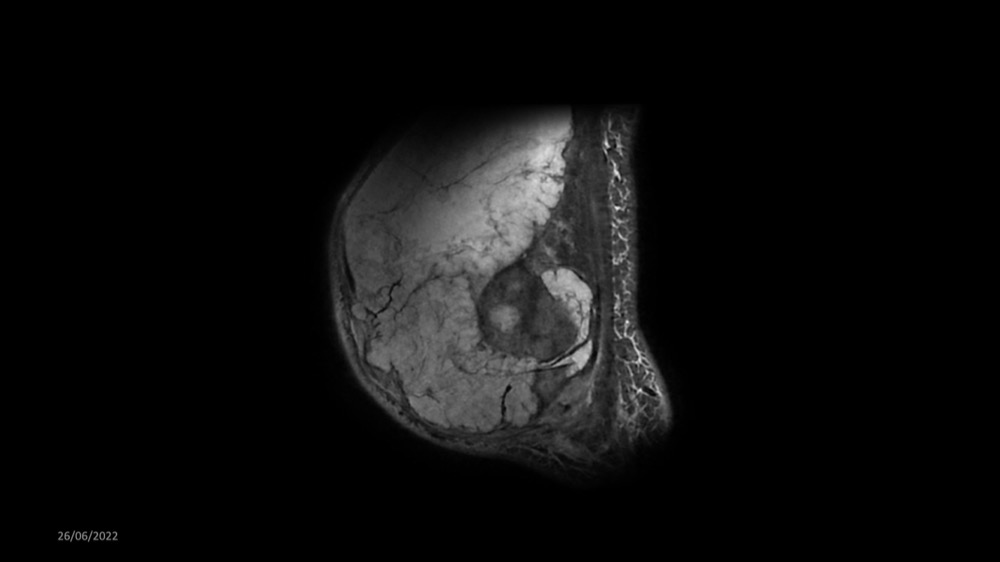

Reichert / Amar / Tordjman / Carlier 29/06/2022